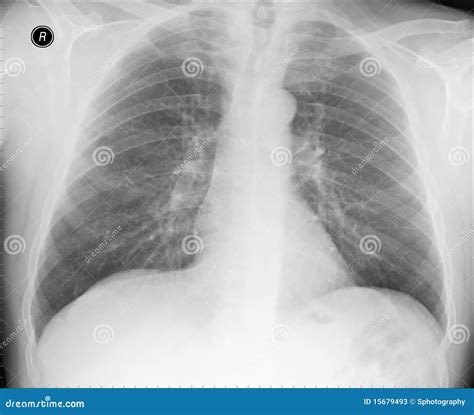

What Does a Normal Lung X-ray Look Like?

A normal lung X-ray typically shows clear lung fields with no signs of inflammation, infection, or other abnormalities. The lungs appear black due to the air they contain, while the heart and other structures appear white. The diaphragm, the muscle that separates the chest from the abdomen, is also visible and should be at a normal level.

Here are some key features of a normal lung X-ray:

• Clear lung fields with no opacities or infiltrates.

• Normal heart size and shape.

• Visible costophrenic angles (the angles where the ribs meet the diaphragm).

• No pleural effusions (fluid accumulation around the lungs).

• Normal vascular markings.